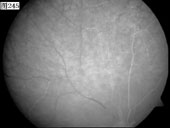

优秀眼底图片奖应征作品展示

17 18 19 20